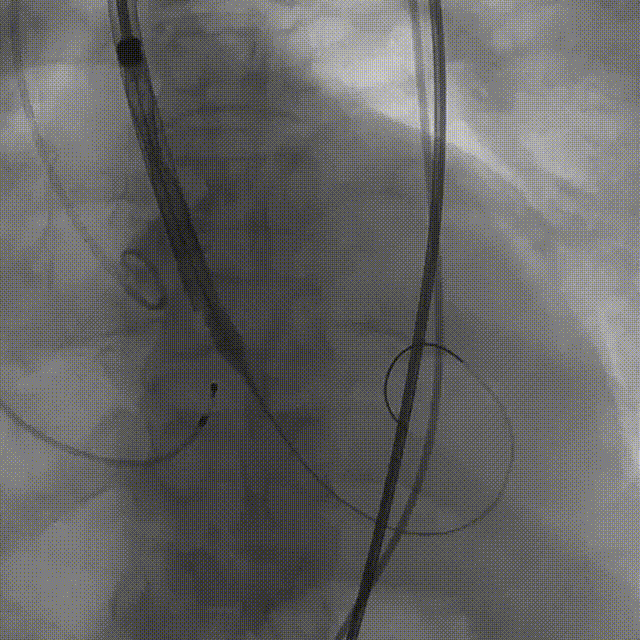

手术影像:

输送器柔顺过弓、跨瓣

瓣膜开始零位定位

瓣膜逐步释放到工作位

工作位造影位置良好

瓣膜逐个脱钩

完全释放后造影,膨胀不良,有漏

25mm球囊后扩

后扩后瓣膜形态良好,造影基本无漏